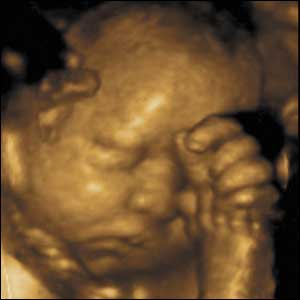

Here's a depiction and a picture of 12 week old fetuses that are now legal to suck out of the uterus and be killed. It's not an issue of privacy nor is it an issue of choice. it's about right and wrong and life and death.